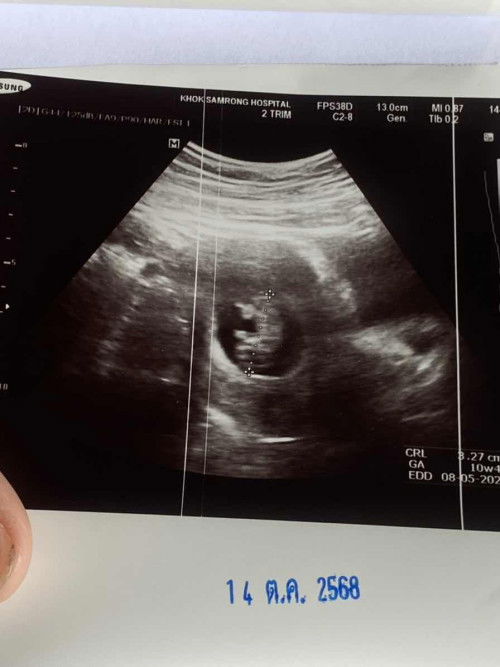

10วีค 1 วัน หมอบอกว่าแขนขายังไม่งอก

แบบนี้ปกติไหมคะหรือเป็นที่เครื่องอันตราซาว แม่กังวลนิดหน่อยคะ ขนาดตัวน้อง 3.27cm